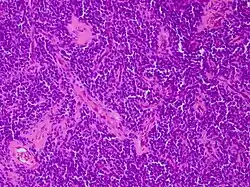

| Micrograph of an H&E stained section of a peripheral PNET. | |

Peripheral PNET

The peripheral PNET (pPNET) is now thought to be virtually identical to Ewing sarcoma:

"Current evidence indicates that both Ewing's sarcoma and PNET have a similar neural phenotype and, because they share an identical chromosome translocation, they should be viewed as the same tumor, differing only in their degree of neural differentiation. Tumors that demonstrate neural differentiation by light microscopy, immunohistochemistry, or electron microscopy have been traditionally labeled PNETs, and those that are undifferentiated by these analyses have been diagnosed as Ewing's sarcoma."[5]